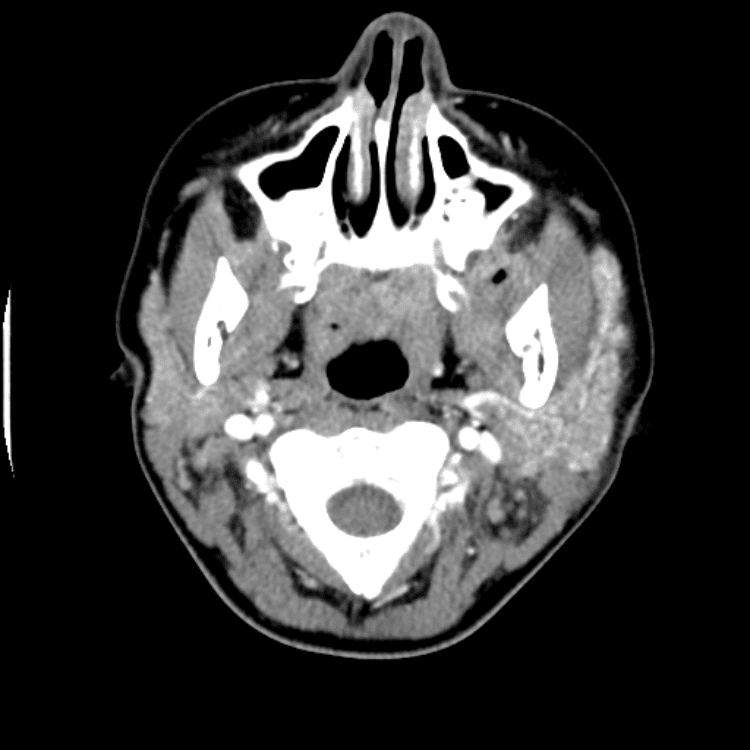

Head and Neck

Practice

Simulates call by including subtle or difficult cases and some normals.

27 cases